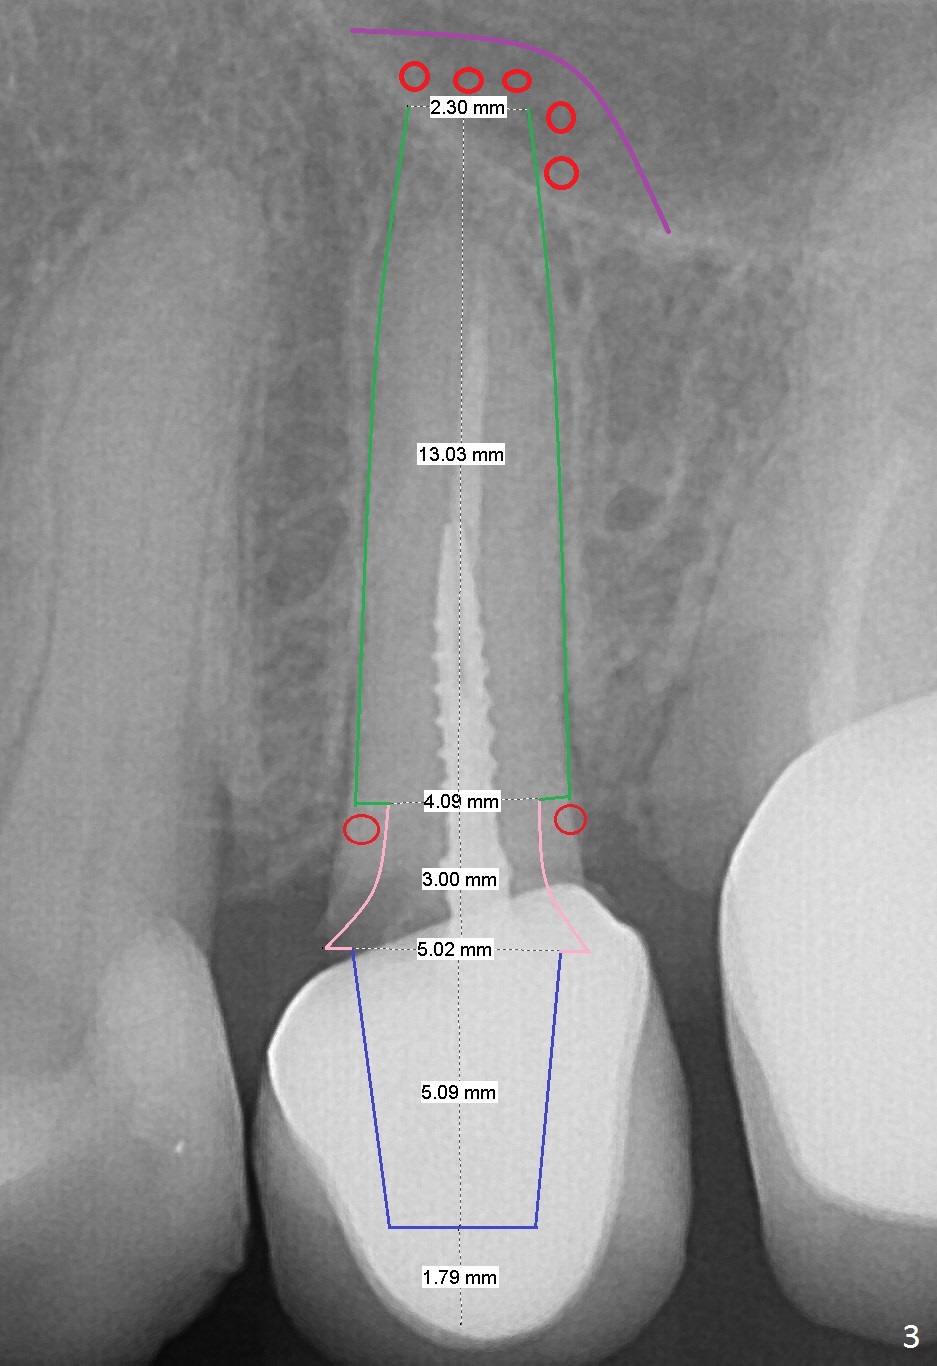

A 60-year-old woman returns to office with chief complaint "upper left crown is loose again".  Clinical exam confirms #13 crown fracture at the gingival level (Fig.1,2 *).  Since the native bone is short, an implant (Fig.3 green) should penetrate the sinus floor for primary stability.  To protect the sinus membrane, PRF membranes (purple curved line) will be inserted prior to bone graft (red circles) and the implant.  A pair abutment is expected to be 5x5 (5.7 exactly, blue) (Fig.3, pink) mm.  The implant should be placed palatally to avoid buccal metal show through.